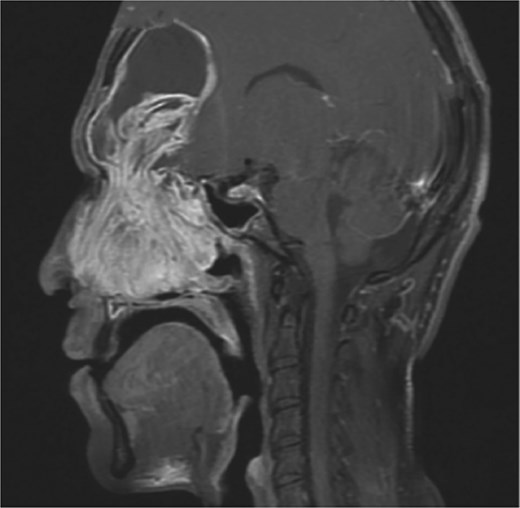

Bilateral extensive nasal polyposis was removed, and pus was drained from the ethmoid sinus cavities using a microdebrider (Fig. 2). Draf type IIb procedure was performed bilaterally to facilitate frontal sinus drainage and ventilation. The procedure was followed by antibiotic-soaked irrigation and evacuation of both mucopyocele cavities. After 6 months, the patient came to the clinic for follow-up, and his repeated CT scans showed normal sinus aeration and complete resolution.

Bilateral frontal sinus showing infected nasal polyps, identified intraoperatively, and drained by image-guided endoscopic sinus surgery.